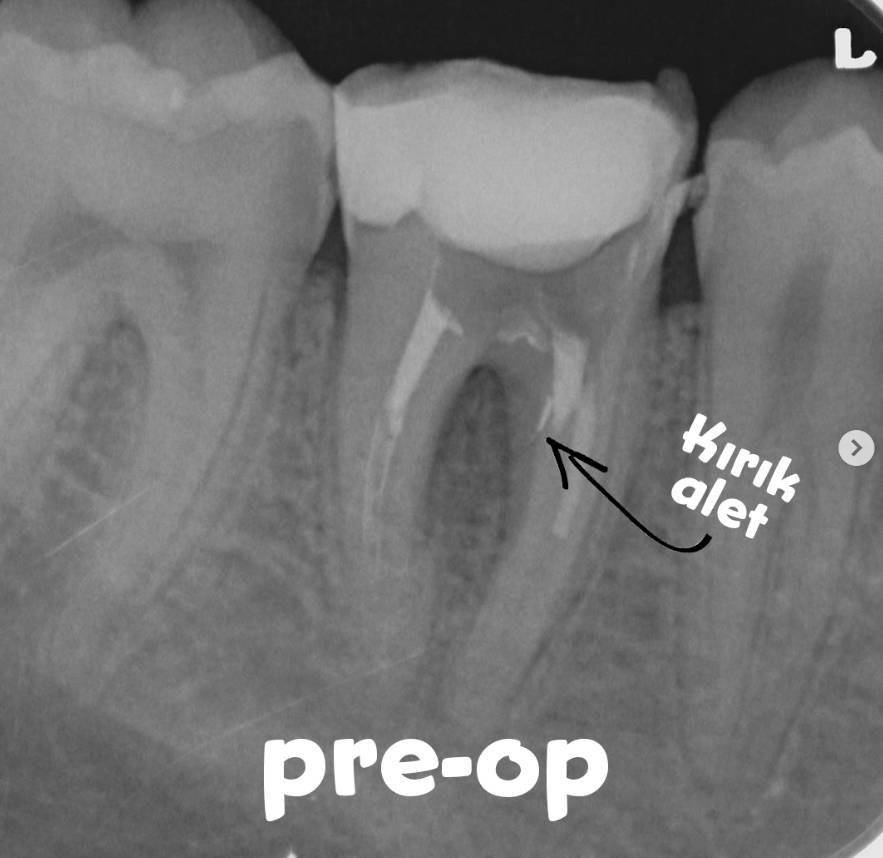

Radiographic and clinical evaluation indicated that a previous retreatment attempt had been made, but the canal filling materials could not be removed.

During the previous procedure, a furcation perforation occurred and a separated instrument was observed in the mesial region.